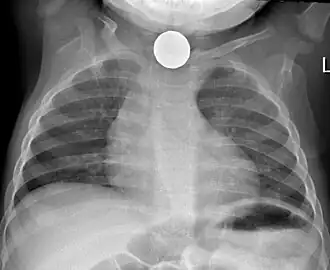

Non-invasive testing

Prior to undertaking endoscopy, attempts should be made to locate the foreign body with x-rays or other non-invasive techniques.[1] For radio-opaque objects, x-rays of the neck, chest and abdomen can be used to locate the foreign body and assist endoscopy.[9] Alternative approaches, including the use of metal detectors, have also been described.[10]

X-rays are also useful for identifying the type of foreign body ingested and complications of foreign body ingestion, including mediastinitis and perforation of the esophagus.[1]